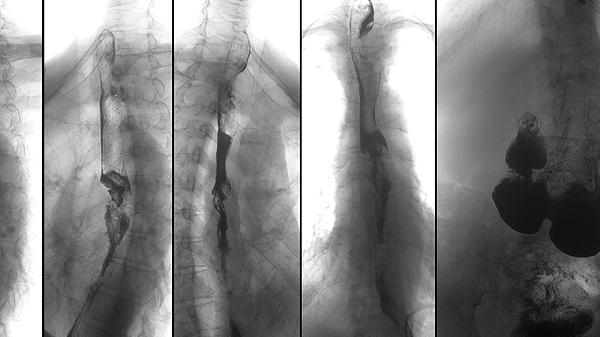

化脓性脊柱炎如何治疗?

最近一段时间这段时间,老是感觉全身上下没劲,头晕乎乎的,尤其后脊柱,就跟针扎的时候,直不起腰来,身上关节处都有疼痛,红肿的症状,大夫说是脊柱炎。脊柱炎是怎么引起的?

"强直性脊柱炎容易引起脊柱僵硬疼痛,影响屈伸活动锻炼,一般多见于自身免疫性疾病可以去医院骨科就诊。抽血检查一下HLAB27

化脓性脊柱炎患者出现脓毒败血症病史通常与细菌感染扩散、免疫力低下或治疗延误等因素有关。化脓性脊柱炎主要由金黄色葡萄球菌等病原体侵袭脊柱引起,若感染未及时控制,细菌可能通过血液循环扩散至全...

化脓性脊柱炎的病因

化脓性脊柱炎应做什么检查确诊

请问一下,化脓性脊柱炎怎么治疗?

化脓性脊柱炎主要由细菌感染引起,常见病原体包括金黄色葡萄球菌、链球菌等,可能通过血行播散、邻近感染扩散或直接外伤感染等途径侵犯脊柱。化脓性脊柱炎可通过血常规检查、影像学检查、病原学检查等方式诊断,需遵医嘱使用抗生素或手术治疗。1.血行播散感染身体其他部位的感染病灶如皮肤疖肿、泌尿系统感染、肺部感染等,细菌可能经血液循环扩散至脊柱。患者常伴有发热、寒战等全身症...